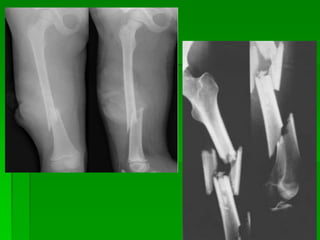

Fémur de Frente AP.

Fémur de Frente : AP

Película: 35x43 Longitudinal

Parilla Antidifusora: Si

Posición del paciente: Decúbito

Dorsal-Supino.

Piernas extendidas en ligera

rotación interna, el trocánter externo.

Pierna contra lateral algo

separada.

El fémur coincidente con la línea

media de la mesa.

Rayo director: Incide en forma

perpendicular al plano de apoyo

haz central sobre

el centro del chasis.

justar el diafragma, identificación de los

lados.

Realizar el disparo con apnea.

Visualización:

El Fémur e toda su extensión. En la

Proyección de frente, se observan

las articulaciones de cadera y de

rodilla.

Si el paciente tiene miembros largos,

una articularon tiene que incluirse.

El trocánter menor no se visualiza.

En caso de Traumatismo: Colocar un soporte debajo de la pierna afectada y la

rodilla, y mantener el pie y el tobillo en una posición AP. Colocar el chasis de

canto contra

la parte interna del muslo para incluir la rodilla, con el haz de rayos en

dirección horizontal desde la parte lateral.

Fractura de fémur